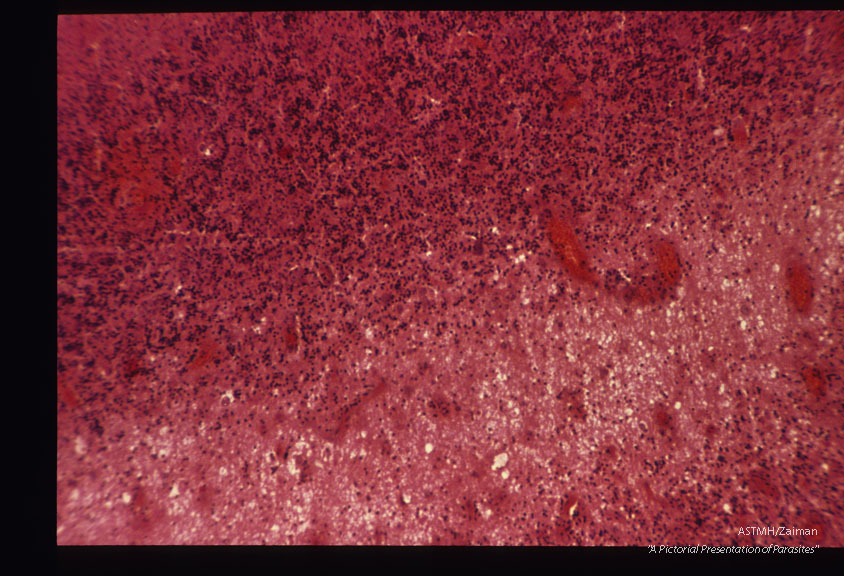

Encephalitis in an East German baby.

Toxoplasma gondii

Description: Encephalitis in an East German baby.